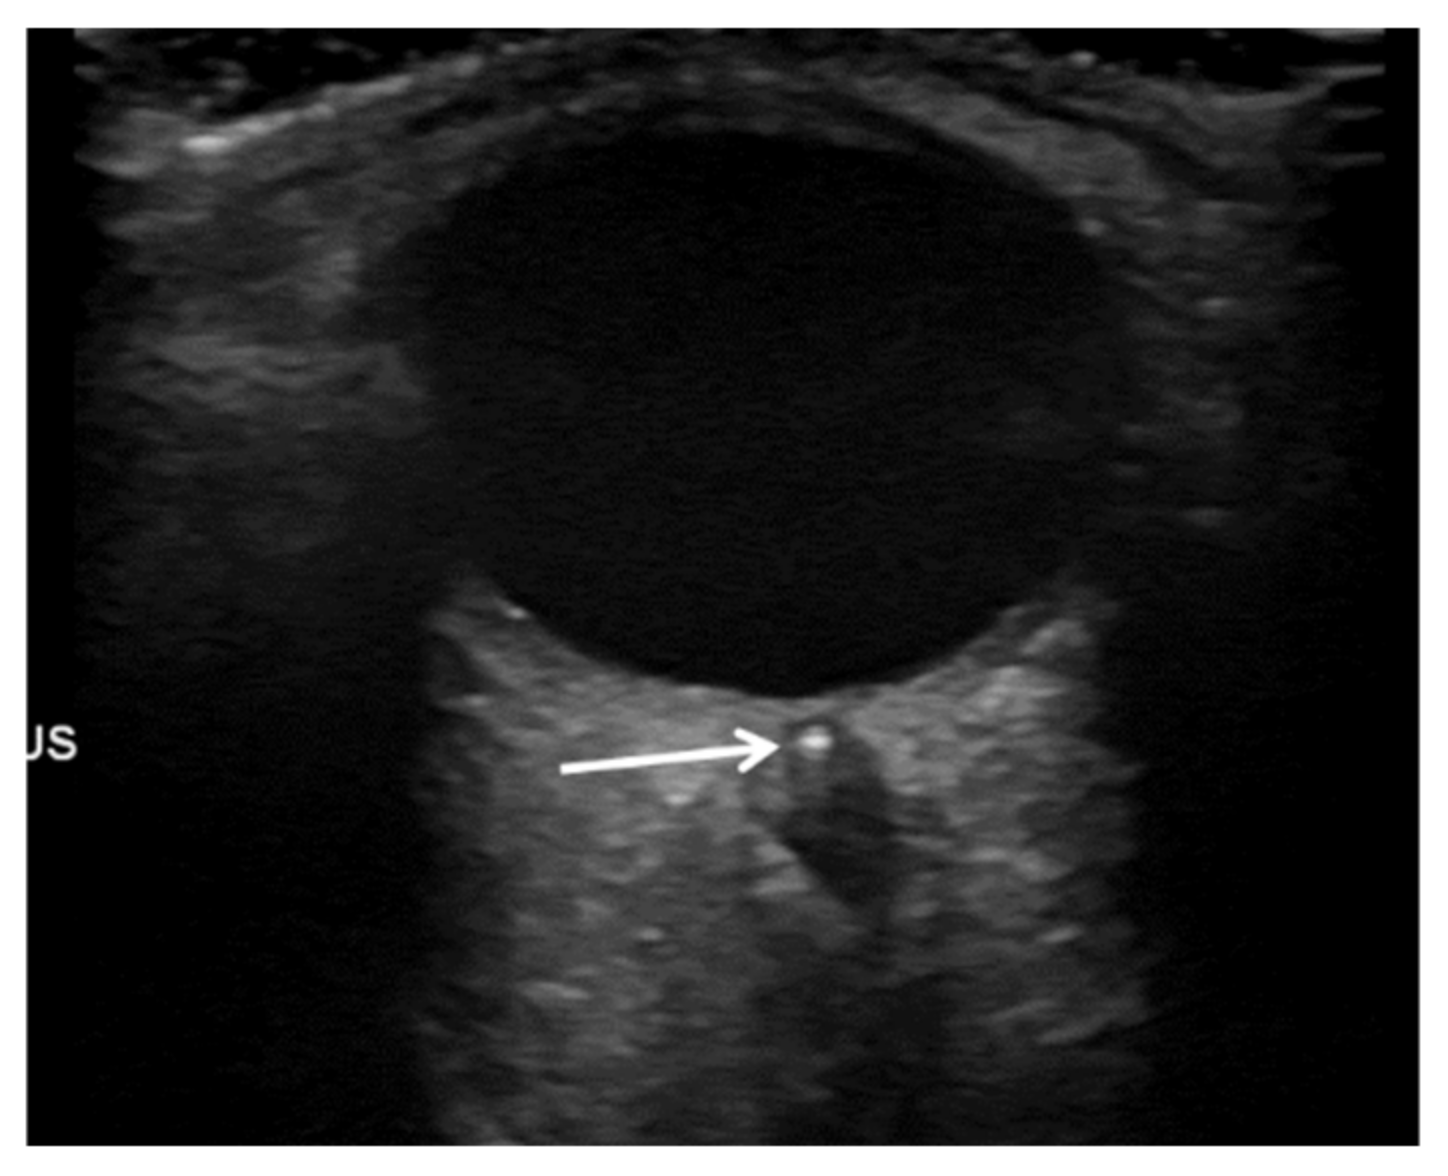

- Ertl, M.; Altmann, M.; Torka, E.; Helbig, H.; Bogdahn, U.; Gamulescu, A.; Schlachetzki, F. The Retrobulbar “Spot Sign” as a Discriminator Between Vasculitic and Thrombo-Embolic Affections of the Retinal Blood Supply. Ultraschall Med. Eur. J. Ultrasound 2012, 33, E263–E267. [Google Scholar] [CrossRef]

- Nedelmann, M.; Graef, M.; Weinand, F.; Wassill, K.-H.; Kaps, M.; Lorenz, B.; Tanislav, C. Retrobulbar Spot Sign Predicts thrombolytic Treatment Effects and Etiology in Central Retinal Artery Occlusion. Stroke 2015, 46, 2322–2324. [Google Scholar] [CrossRef]

- Smith, A.T.; Wilbert, C.D.; Ferre, R.M. Using the Retrobulbar Spot Sign to Assist in Diagnosis and Management of Central Retinal Artery Occlusions. J. Ultrasound Med. Off. J. Am. Inst. Ultrasound Med. 2020, 39, 197–202. [Google Scholar] [CrossRef]

- Altmann, M.; Ertl, M.; Helbig, H.; Schömig, B.; Bogdahn, U.; Gamulescu, M.-A.; Schlachetzki, F. Low Endogenous Recanalization in Embolic Central Retinal Artery Occlusion—The Retrobulbar “Spot Sign”. J. Neuroimaging 2015, 25, 251–256. [Google Scholar] [CrossRef]